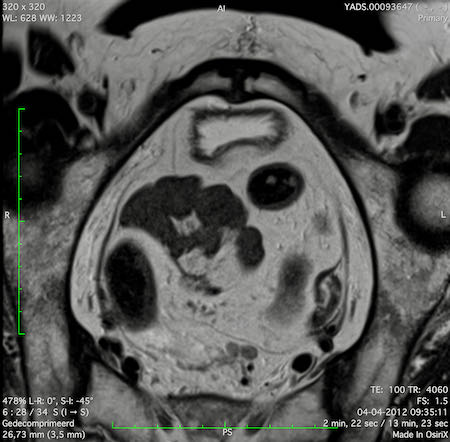

Hình ảnh

Các hình ảnh được cung cấp cho thấy ung thư biểu mô tế bào nhẫn với tình trạng dày lan tỏa thành trực tràng, hình ảnh bia bắn điển hình, và sự xâm lấn mỡ mạc treo trực tràng.